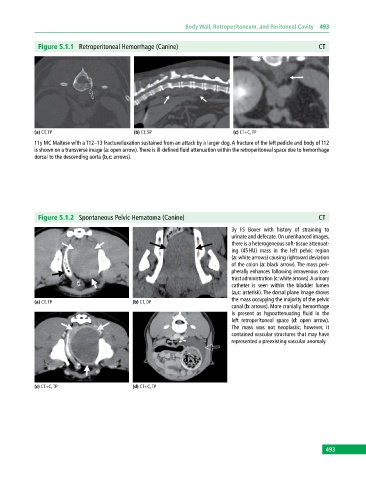

Figure 5.1.1 Retroperitoneal Hemorrhage (Canine) CT

(a) CT, TP (b) CT, SP (c) CT+C, TP

11y MC Maltese with a T12–13 fracture/luxation sustained from an attack by a larger dog. A fracture of the left pedicle and body of T12

is shown on a transverse image (a: open arrow). There is ill‐defined fluid attenuation within the retroperitoneal space due to hemorrhage

dorsal to the descending aorta (b,c: arrows).

Figure 5.1.2 Spontaneous Pelvic Hematoma (Canine) CT

3y FS Boxer with history of straining to

urinate and defecate. On unenhanced images,

there is a heterogeneous soft‐tissue attenuat

ing (45 HU) mass in the left pelvic region

(a: white arrows) causing rightward deviation

of the colon (a: black arrow). The mass peri

pherally enhances following intravenous con

trast administration (c: white arrows). A urinary

catheter is seen within the bladder lumen

(a,c: asterisk). The dorsal plane image shows

the mass occupying the majority of the pelvic

canal (b: arrows). More cranially, hemorrhage

is present as hypoattenuating fluid in the

left retroperitoneal space (d: open arrow).

The mass was not neoplastic; however, it

contained vascular structures that may have

represented a preexisting vascular anomaly.